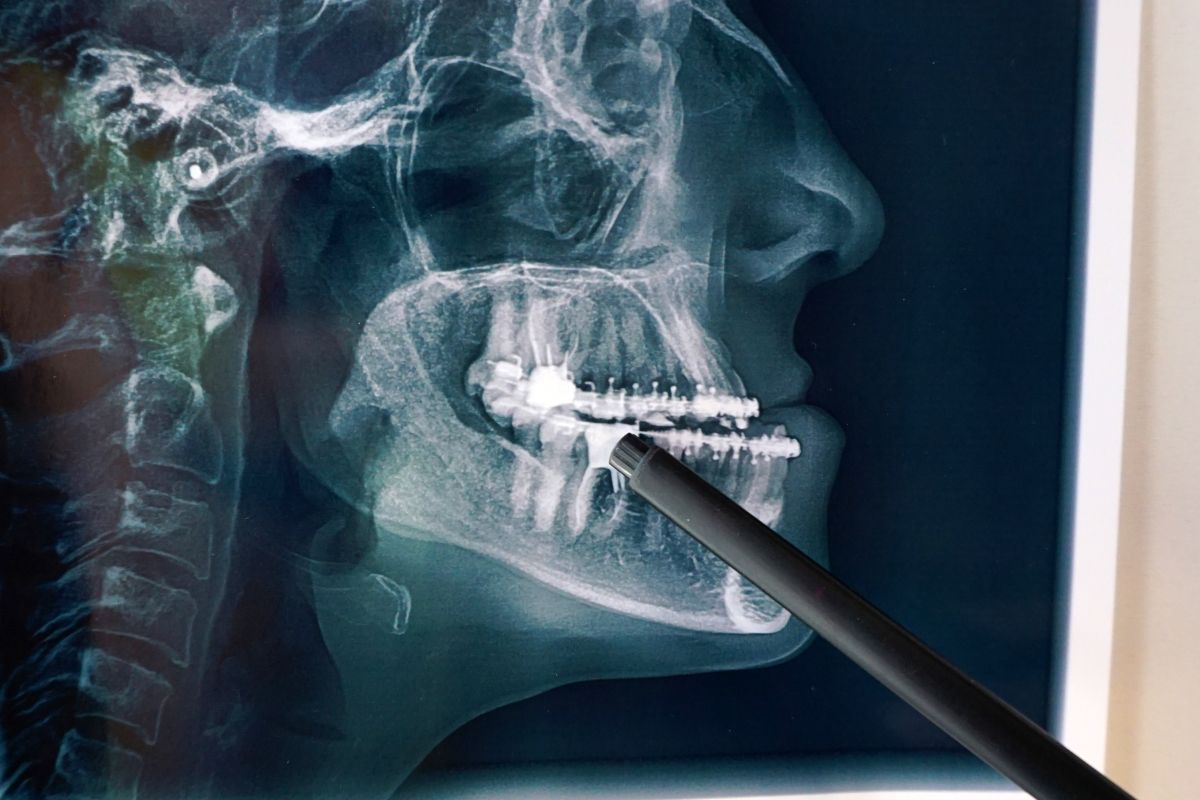

La cirugía maxilofacial es una especialidad que abarca diagnósticos y tratamientos de enfermedades, lesiones y defectos en la cabeza, el cuello, la cara, los maxilares y los tejidos duros y blandos de la región oral y maxilofacial. Este procedimiento suele ser necesario para corregir problemas de masticación, estética facial o condiciones patológicas.

La cirugía maxilofacial actúa en diversas áreas, incluyendo el tratamiento de traumatismos faciales, deformidades congénitas, disfunciones de la articulación temporomandibular y enfermedades de los tejidos orales, entre otras. Los especialistas en este campo están capacitados no solo en odontología, sino también en cirugía, lo que les confiere un conjunto de habilidades únicas para manejar estos problemas complejos.

El proceso comienza con una evaluación detallada por parte de un cirujano maxilofacial, quien planificará la cirugía basada en las necesidades específicas de cada paciente. Dependiendo del caso, la intervención puede variar desde cirugías menores en la cavidad oral, que se realizan de manera ambulatoria, hasta procedimientos más complejos que requieren hospitalización. Tras la operación, la fase de recuperación es crucial e implicará seguimiento para asegurar una correcta cicatrización y funcionalidad.

La preparación para la cirugía maxilofacial suele incluir estudios de imagen, revisión de la historia clínica del paciente y, en ocasiones, la colaboración con otros especialistas como ortodoncistas o anestesiólogos. La recuperación variará según el tipo de cirugía, pero generalmente incluye una dieta blanda durante las primeras semanas y visitas regulares al cirujano para monitorear el progreso. También es fundamental seguir todas las indicaciones médicas para evitar complicaciones y acelerar la recuperación.